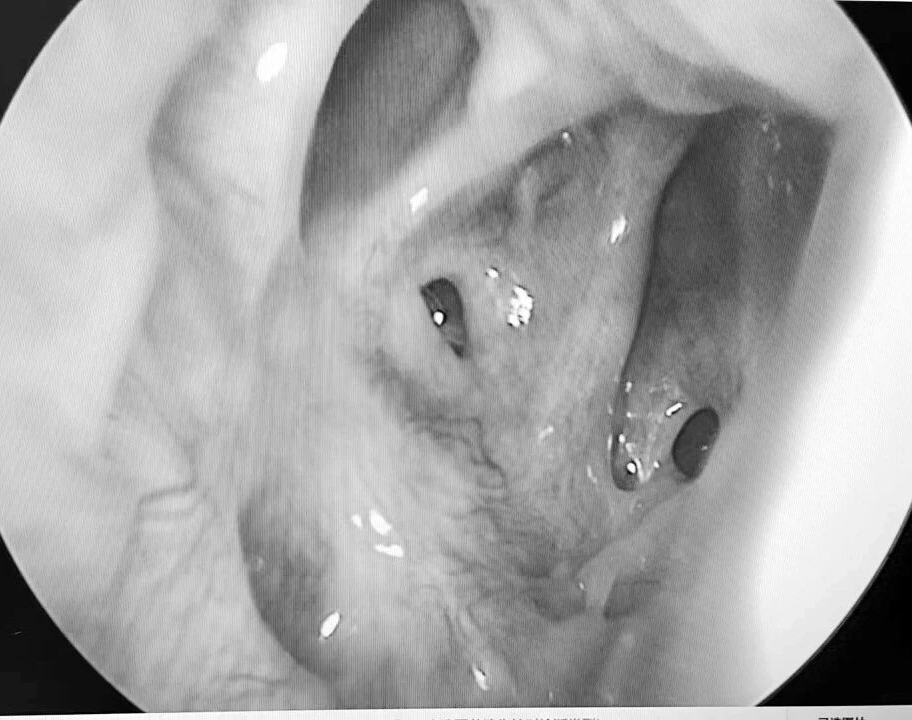

患者梁某(化名)因反复鼻塞、流脓涕伴头痛2月余入院,经检查确诊为急性鼻窦炎、双侧乳突炎,药物治疗后症状未缓解且并发筛窦脓肿到我院耳鼻咽喉科二区住院,科室团队快速完成术前评估,为患者制定个性化手术方案,在全麻下精准实施经鼻内镜手术,开放病变窦腔、清理脓液,术中损伤小,仅用吸收性明胶海绵止血。术后通过专业的鼻腔冲洗指导、药物治疗管理及定期内镜复查,有效促进术腔黏膜修复,降低复发风险,助力患者实现快速康复。

我院耳鼻咽喉科二区以微创内镜手术为特色,面对急性鼻窦脓肿这类需及时干预的病症,能通过高效术前评估、优化手术流程,精准去除病灶,避免并发症发生。手术前后规范用药配合专业术后护理,包括鼻腔冲洗指导与定期内镜复查,有效降低复发风险,践行快速康复外科理念。